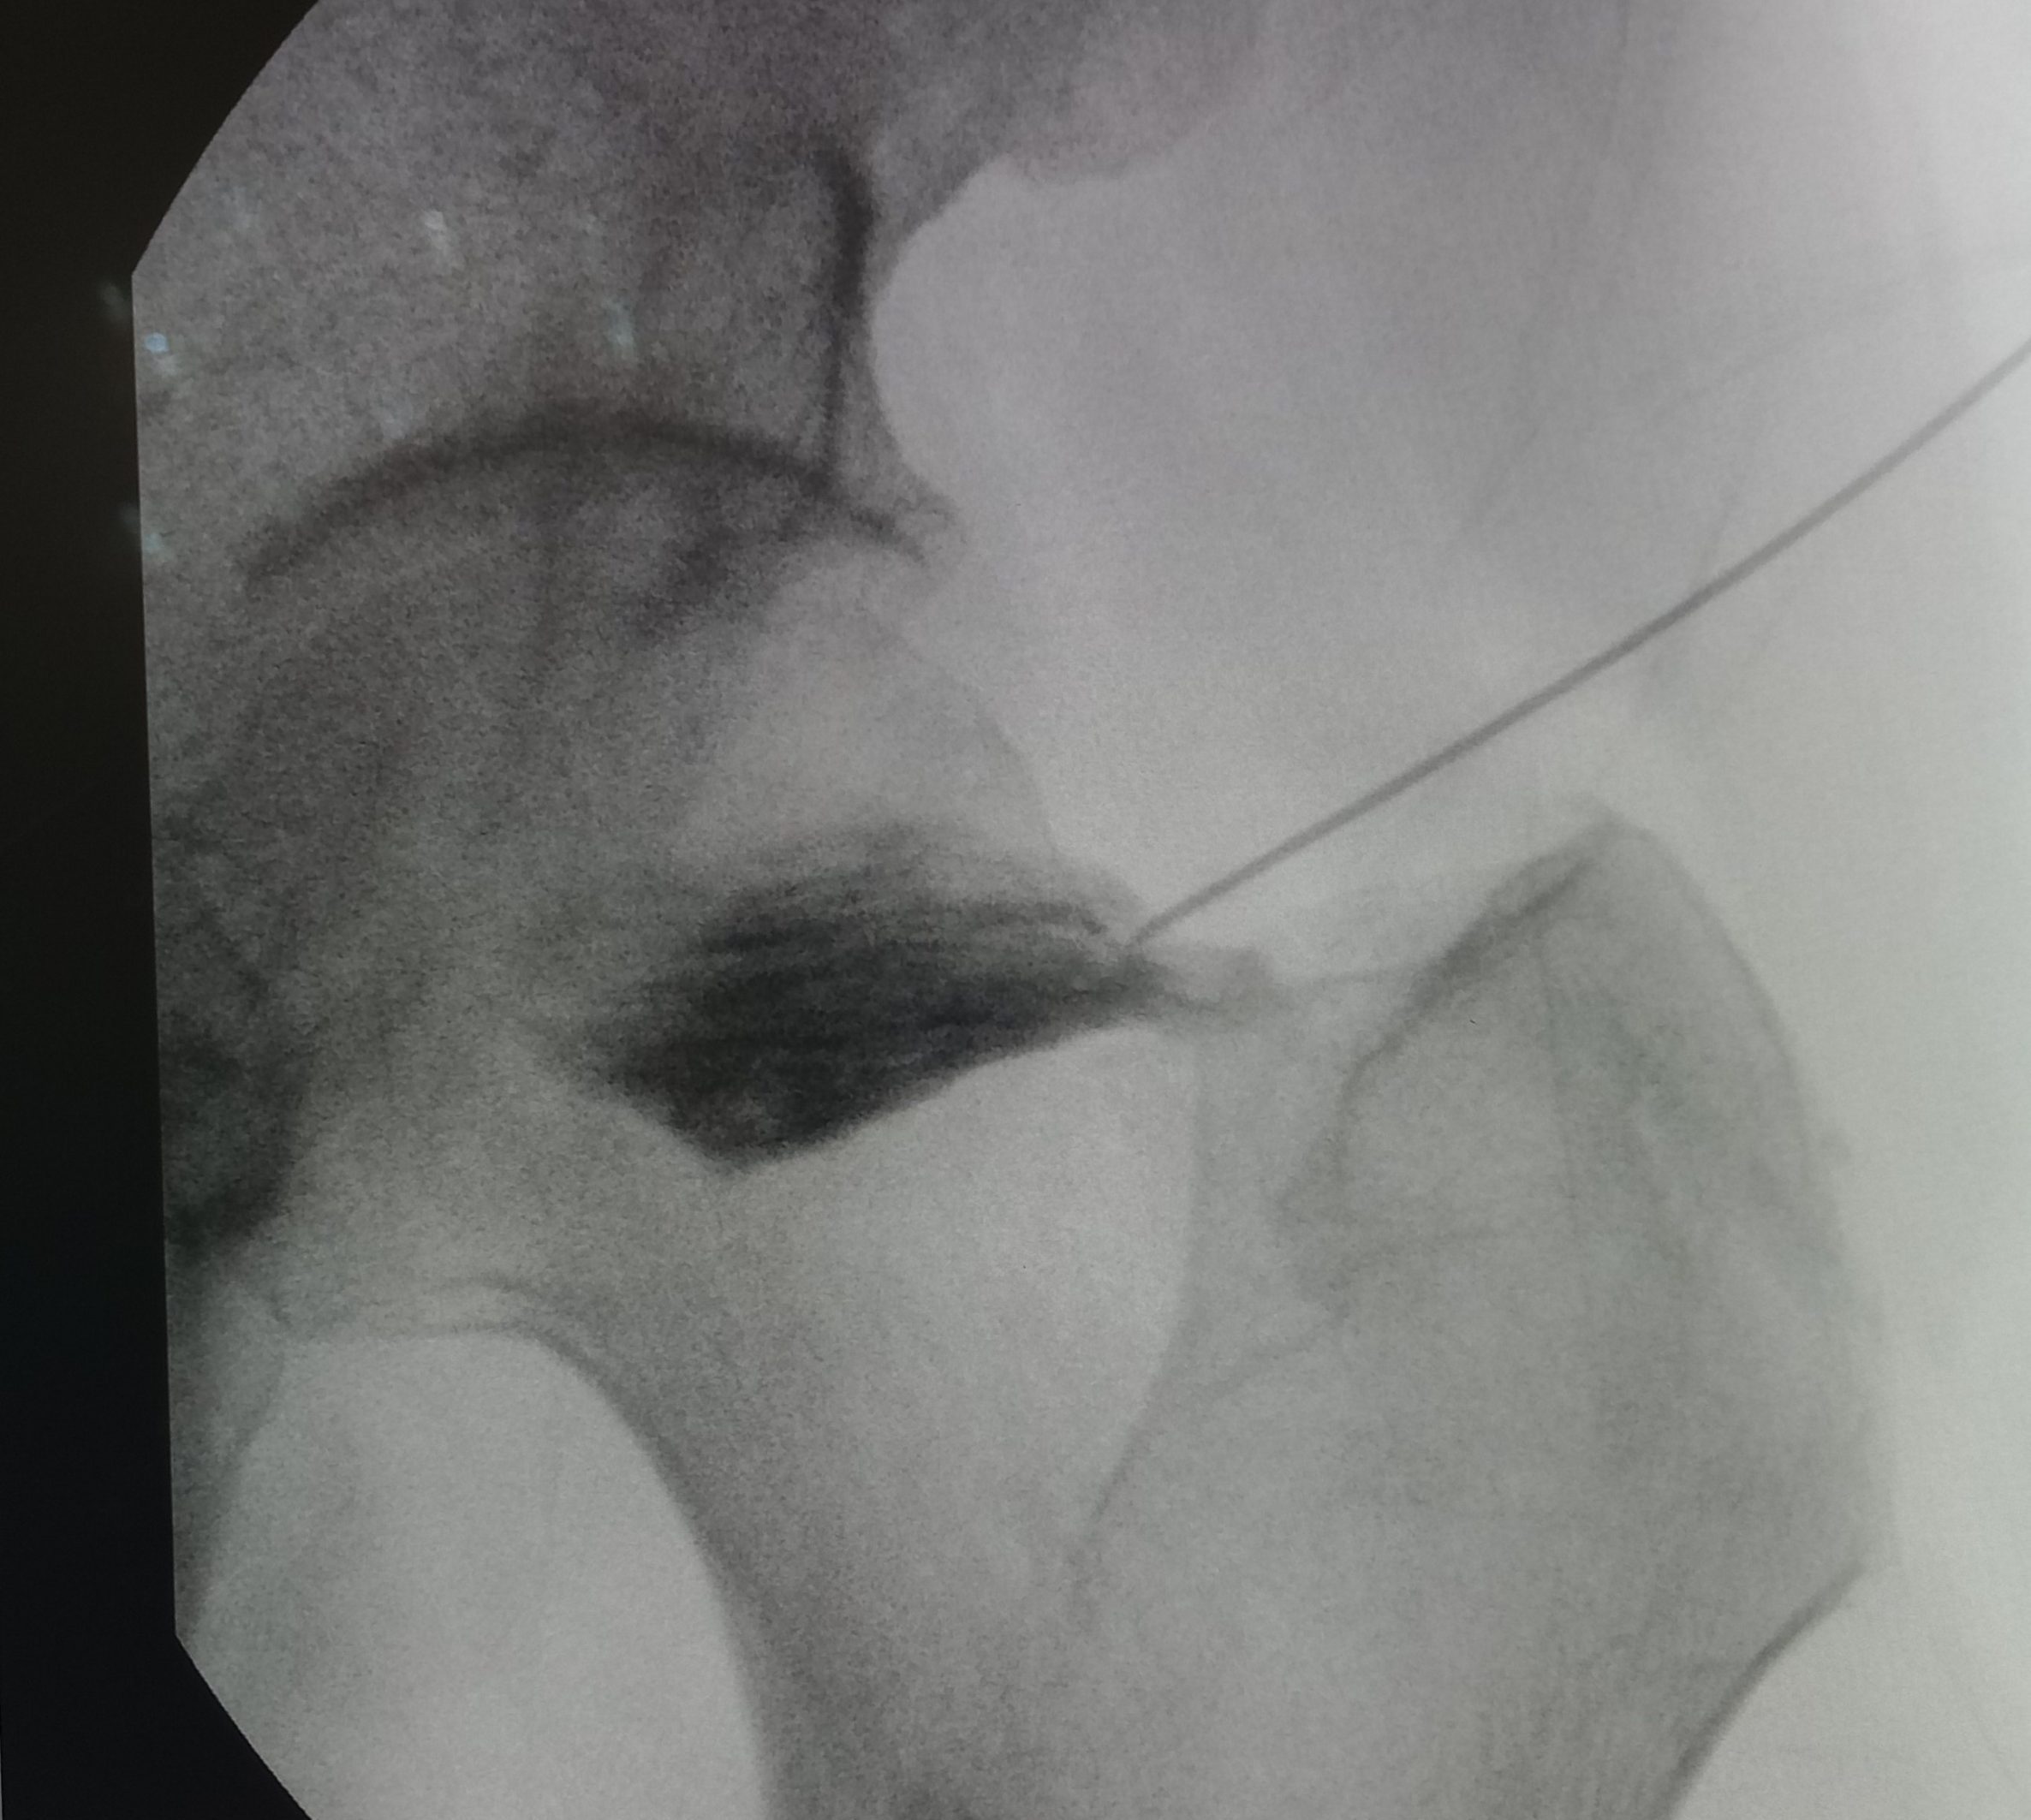

Ασθενής με άλγος δεξιού ισχίου

Ασθενής 53 ετών, γυμνάστρια, με αιφνίδιο άλγος δεξιού ισχίου από 2ετίας. Υπεβλήθη σε διάφορες θεραπείες σε άλλα κέντρα χωρίς αποτέλεσμα. Η ακτινογραφία έδειξε ότι υπάρχει οστεοαρθρίτιδα με αρθροκατατάδυση. Λόγω του νεαρού της ηλικίας απεφασίσθη να μην υποβληθεί σε ολική αρθροπλαστική. Πραγματoποιήθηκε έγχυση ισχίου με υαλουρονικό και τοπικό αναισθητικό. Η ασθενής ένιωσε άμεσα ανακούφιση που διατηρείται έως σήμερα 2 χόνια μετά